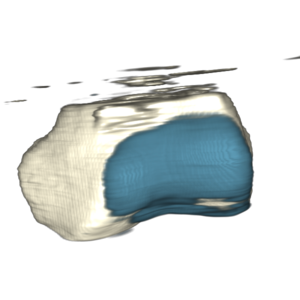

- analysis of cartilage thickness for ostheoarthitis assessment

- patellofemoral joint (prospective motion correction)

- depicted image is a healthy volunteer